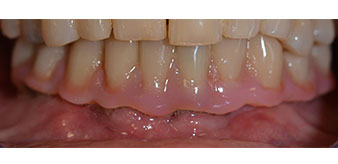

След това е взет отпечатък и е определена захапката на пациента, за да може зъботехникът незабавно да започне изработването на временната протеза. Протезата е поставена в същия ден (Фиг. 17 и 18).

След изчакване на необходимото време за осеоинтеграция, финалният отпечатък на имплантите е свален и следователно е изработена финалната протеза (Фиг. 19 и 20). В този момент, лекарят по дентална медицина и пациентът могат да обсъдят дали да използват керамични или пластмасови фасети и циркониева или метална рамка. В този случай, екипът на д-р Паску избира пластмасови фасети, имайки предвид неясната прогноза относно частичното обеззъбяване в челюстта и фактът, че зъб 24 е прорастнал. Този вид протеза обикновено е по-лесна за адаптиране и впоследствие може да бъде променяна спрямо новата ситуация в челюстта.